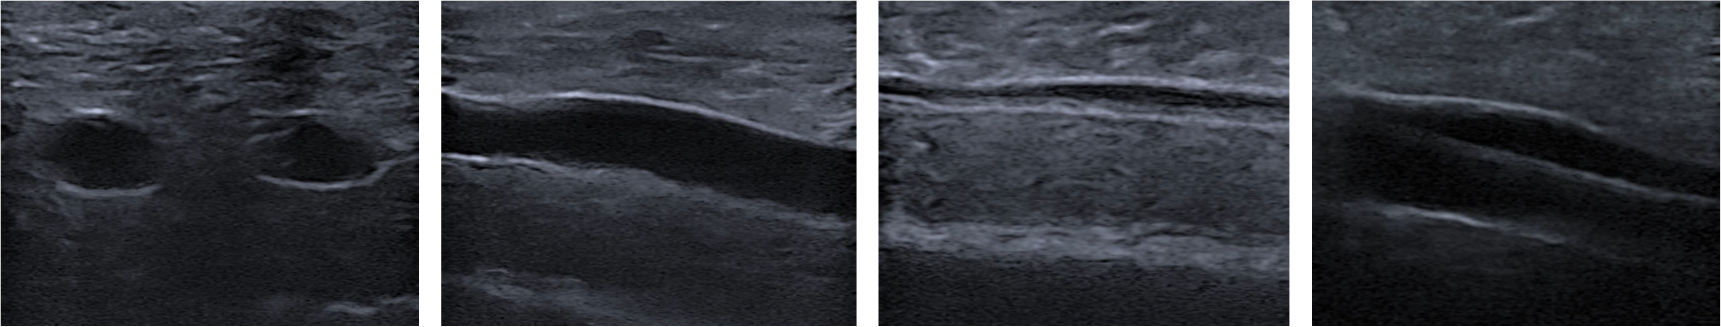

Sua anatomia representa de forma realística as texturas de pele e reproduz fielmente as propriedades acústicas na região jugular, podendo ser observados internamente seus tecidos e veias por meio de equipamentos de ultrassonografia.

Na Artéria pode-se identificar sua pulsação e resistência a compressão.

A Veia Jugular poder ser colabada e puncionada, sendo possível sua aspiração e injeção.